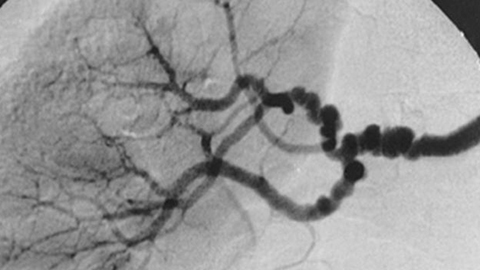

Black and white image of blood vessels under a microscope.

0:13:18.8 RW: So this condition is usually diagnosed with the use of imaging, including computed tomography and geography, that's a CTA or specialized ultrasound or some other kinds of tests. FMD has a particular appearance in the arteries that it effects, it makes these tight spots and these little aneurysms so what you get are several bulges in a row that looks like a string of beads. The Cleveland Clinic article that I used to help me get this information has a gorgeous example of this image, and you'll find a link to it in the show notes, I promise, it is worth a look. It's worth pursuing a diagnosis if someone is having these signs and symptoms, because FMD can look like some other things. It can look like typical atherosclerosis with hypertension, it can look like a sub-type of Ehlers-Danlos syndrome that also involves weakened blood vessels or another inherited connective tissue disorder called Marfan syndrome.